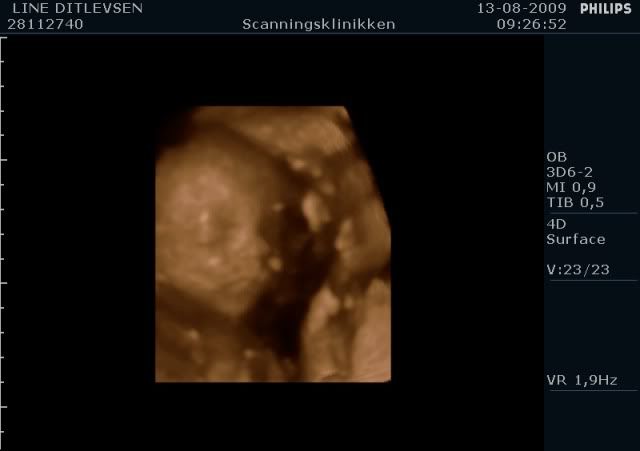

Jeg har lige været til en 3D/4D scanning (27+0), hvilket var en kæmpe oplevelse. Jeg venter en dreng på foreløbig 976 gram

Denne tråd er for alle os som har fået foretaget sådan en scanning. Jeg tænkte det kunne være sjovt at smide nogle fotos op af vores bebzere, da de lå i maven. I profil og forfra.

Skriv gerne hvilken uge scanningen er foretaget, samt evt. hvad køn det er